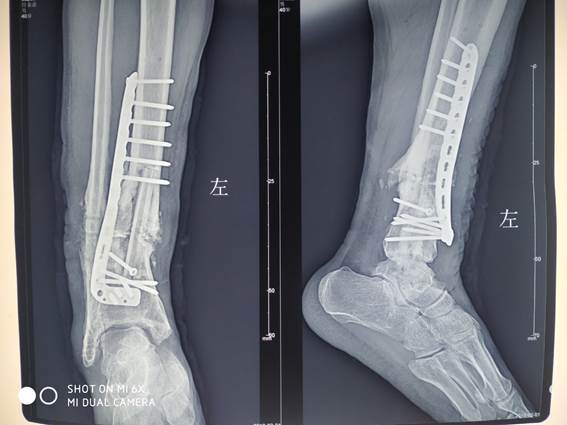

▲患者术前影像资料

刘占宏主任从患者影像分析:患者左腓骨内固定断裂,左胫骨骨不连,骨折部位已形成骨痂,骨折部位不愈合是引起患者疼痛的主要原因。鉴于患者病情比较复杂,刘占宏主任带领诺贝尔医院骨科团队认真研究、制定了周密的手术方案:

第一、要从右腿截一块带有血管蒂游离的腓骨,移植到左腿;

第二、左腿切开复位,取出断裂的内固定;

第三、把之前骨不连的地方的已经钙化形成骨痂的骨头去除,移植腓骨;

第四、由于是患腿,术后近四年,已形成斑块,血管需要一个一个剥离出来,在显微镜下和移植的腓骨血管再进行缝合;

第五、加内固定固定骨折部位。